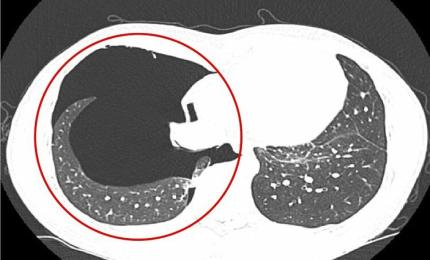

Đẩy tạ quá sức, nam thanh niên tràn khí màng phổi

Ngày 19/6, đại diện Bệnh viện Đa khoa Medlatec cho biết bệnh nhân tiền sử khỏe mạnh, không bị bệnh phổi.